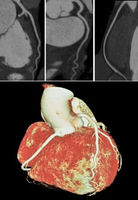

Kardiale CT bei einem 49-jährigen Patienten mit typischen, belastungsabhängigen Thoraxschmerzen. Kalk-Score-Bestimmung: Gesamtscore 58 (entspricht der 50. altersgenormten Perzentile, nicht dargestellt).

CT-Angiographie: Nachweis einer hochgradigen Engestelle des linken Herzkranzgefäßes (proximale LAD-Stenose, vgl. Bilder). Aufgrund dieses Befundes wurde eine Herzkatheteruntersuchung durchgeführt und der Patient mit einem Stent versorgt.